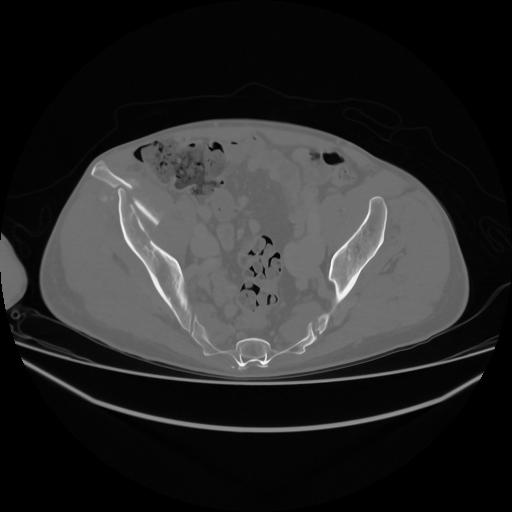

5 CUERPO,CE,Vol,1.0,CUERPO,,